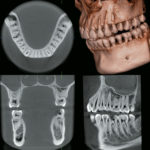

Macizo Facial